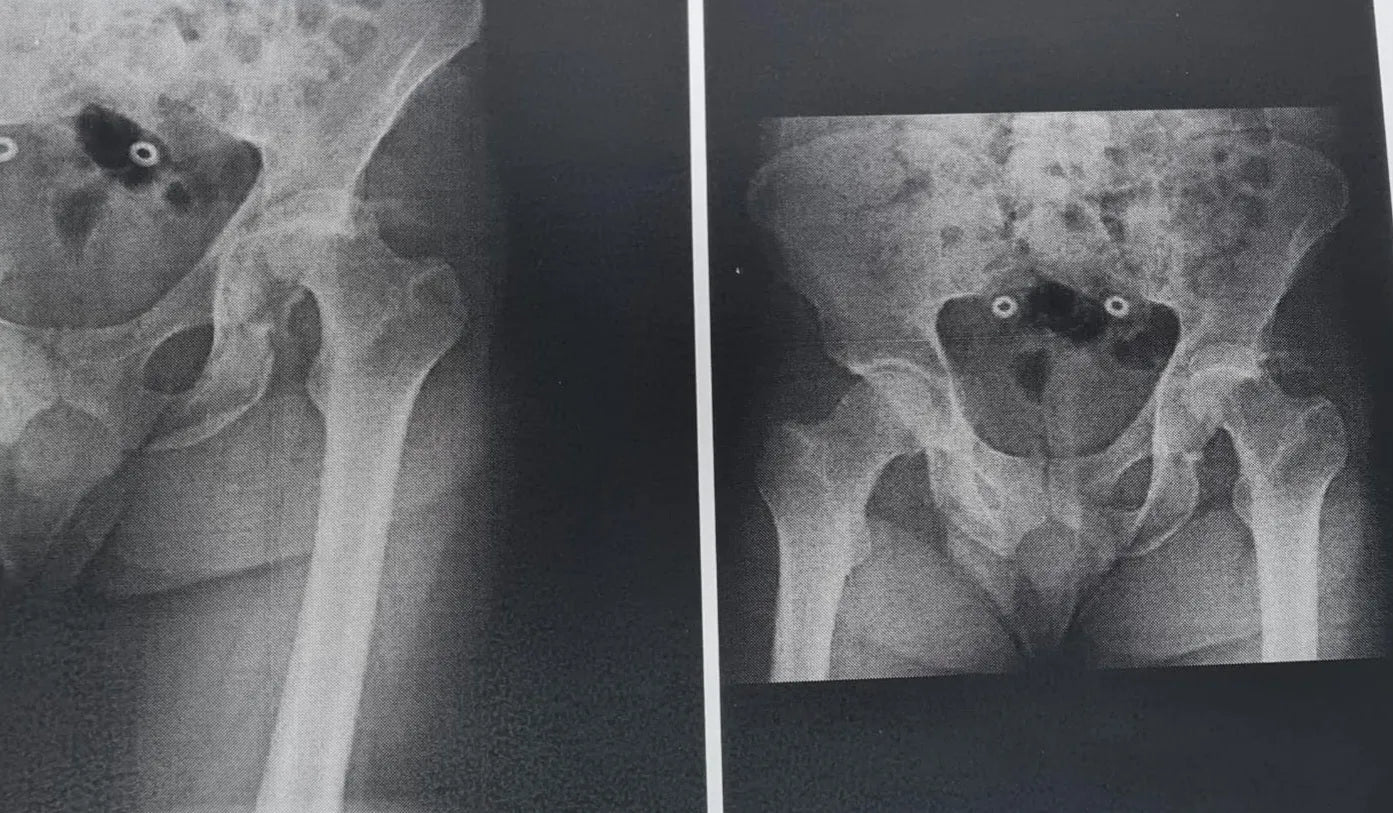

Fratura do Rebordo Posterior do Acetábulo com Luxação do Quadril

Domine o tratamento de fraturas do rebordo posterior do acetábulo associadas à luxação do quadril. Este treinamento oferece uma imersão técnica em uma abordagem cirúrgica cuidadosamente planejada e executada, visando a redução dos fragmentos, a fixação para restabelecer a congruência articular e a estabilidade do quadril.

- Tratamento cirúrgico de fraturas do rebordo posterior do acetábulo com luxação do quadril.

- Avaliação Inicial e Acesso Cirúrgico Otimizado: Aprenda a interpretar tomografias computadorizadas para identificar luxação do quadril e grandes fragmentos do rebordo posterior do acetábulo. Domine o acesso de Kocher-Langenbeck, utilizando pontos de referência como o ápice do trocânter maior, a espinha ilíaca póstero-superior e o eixo longo do fêmur.

- Identificação e Redução Precisa dos Fragmentos: Saiba como identificar os fragmentos inferior e superior do teto acetabular. Aprenda a limpar e descolar a articulação para melhor identificação dos parâmetros de redução, e reposicionar os fragmentos em seus locais anatômicos após a redução da luxação.